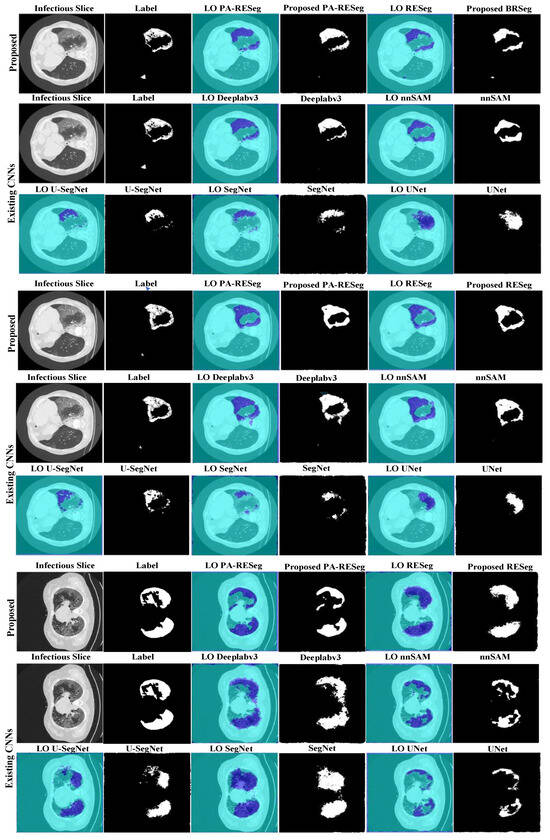

5.2.1. Proposed RESeg Segmentation Analysis

5.2.2. Segmentation Stage Performance Comparison

5.2.3. Pixel Attention Concept